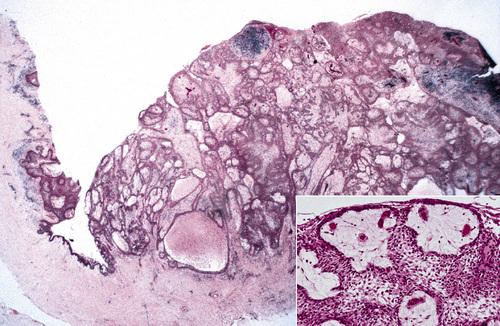

Histopathologic Features

- keratocysts with a fibrous capsule having more:

- satellite cysts

- islands of epithelial proliferation

- odontogenic epithelial rests

- foci of calcification also appear to be more common

Odontogenic keratocyst (OKC) showing numerous odontogenic epithelial rests in the cyst wall.

nevoid basal cell carcinoma syndrome